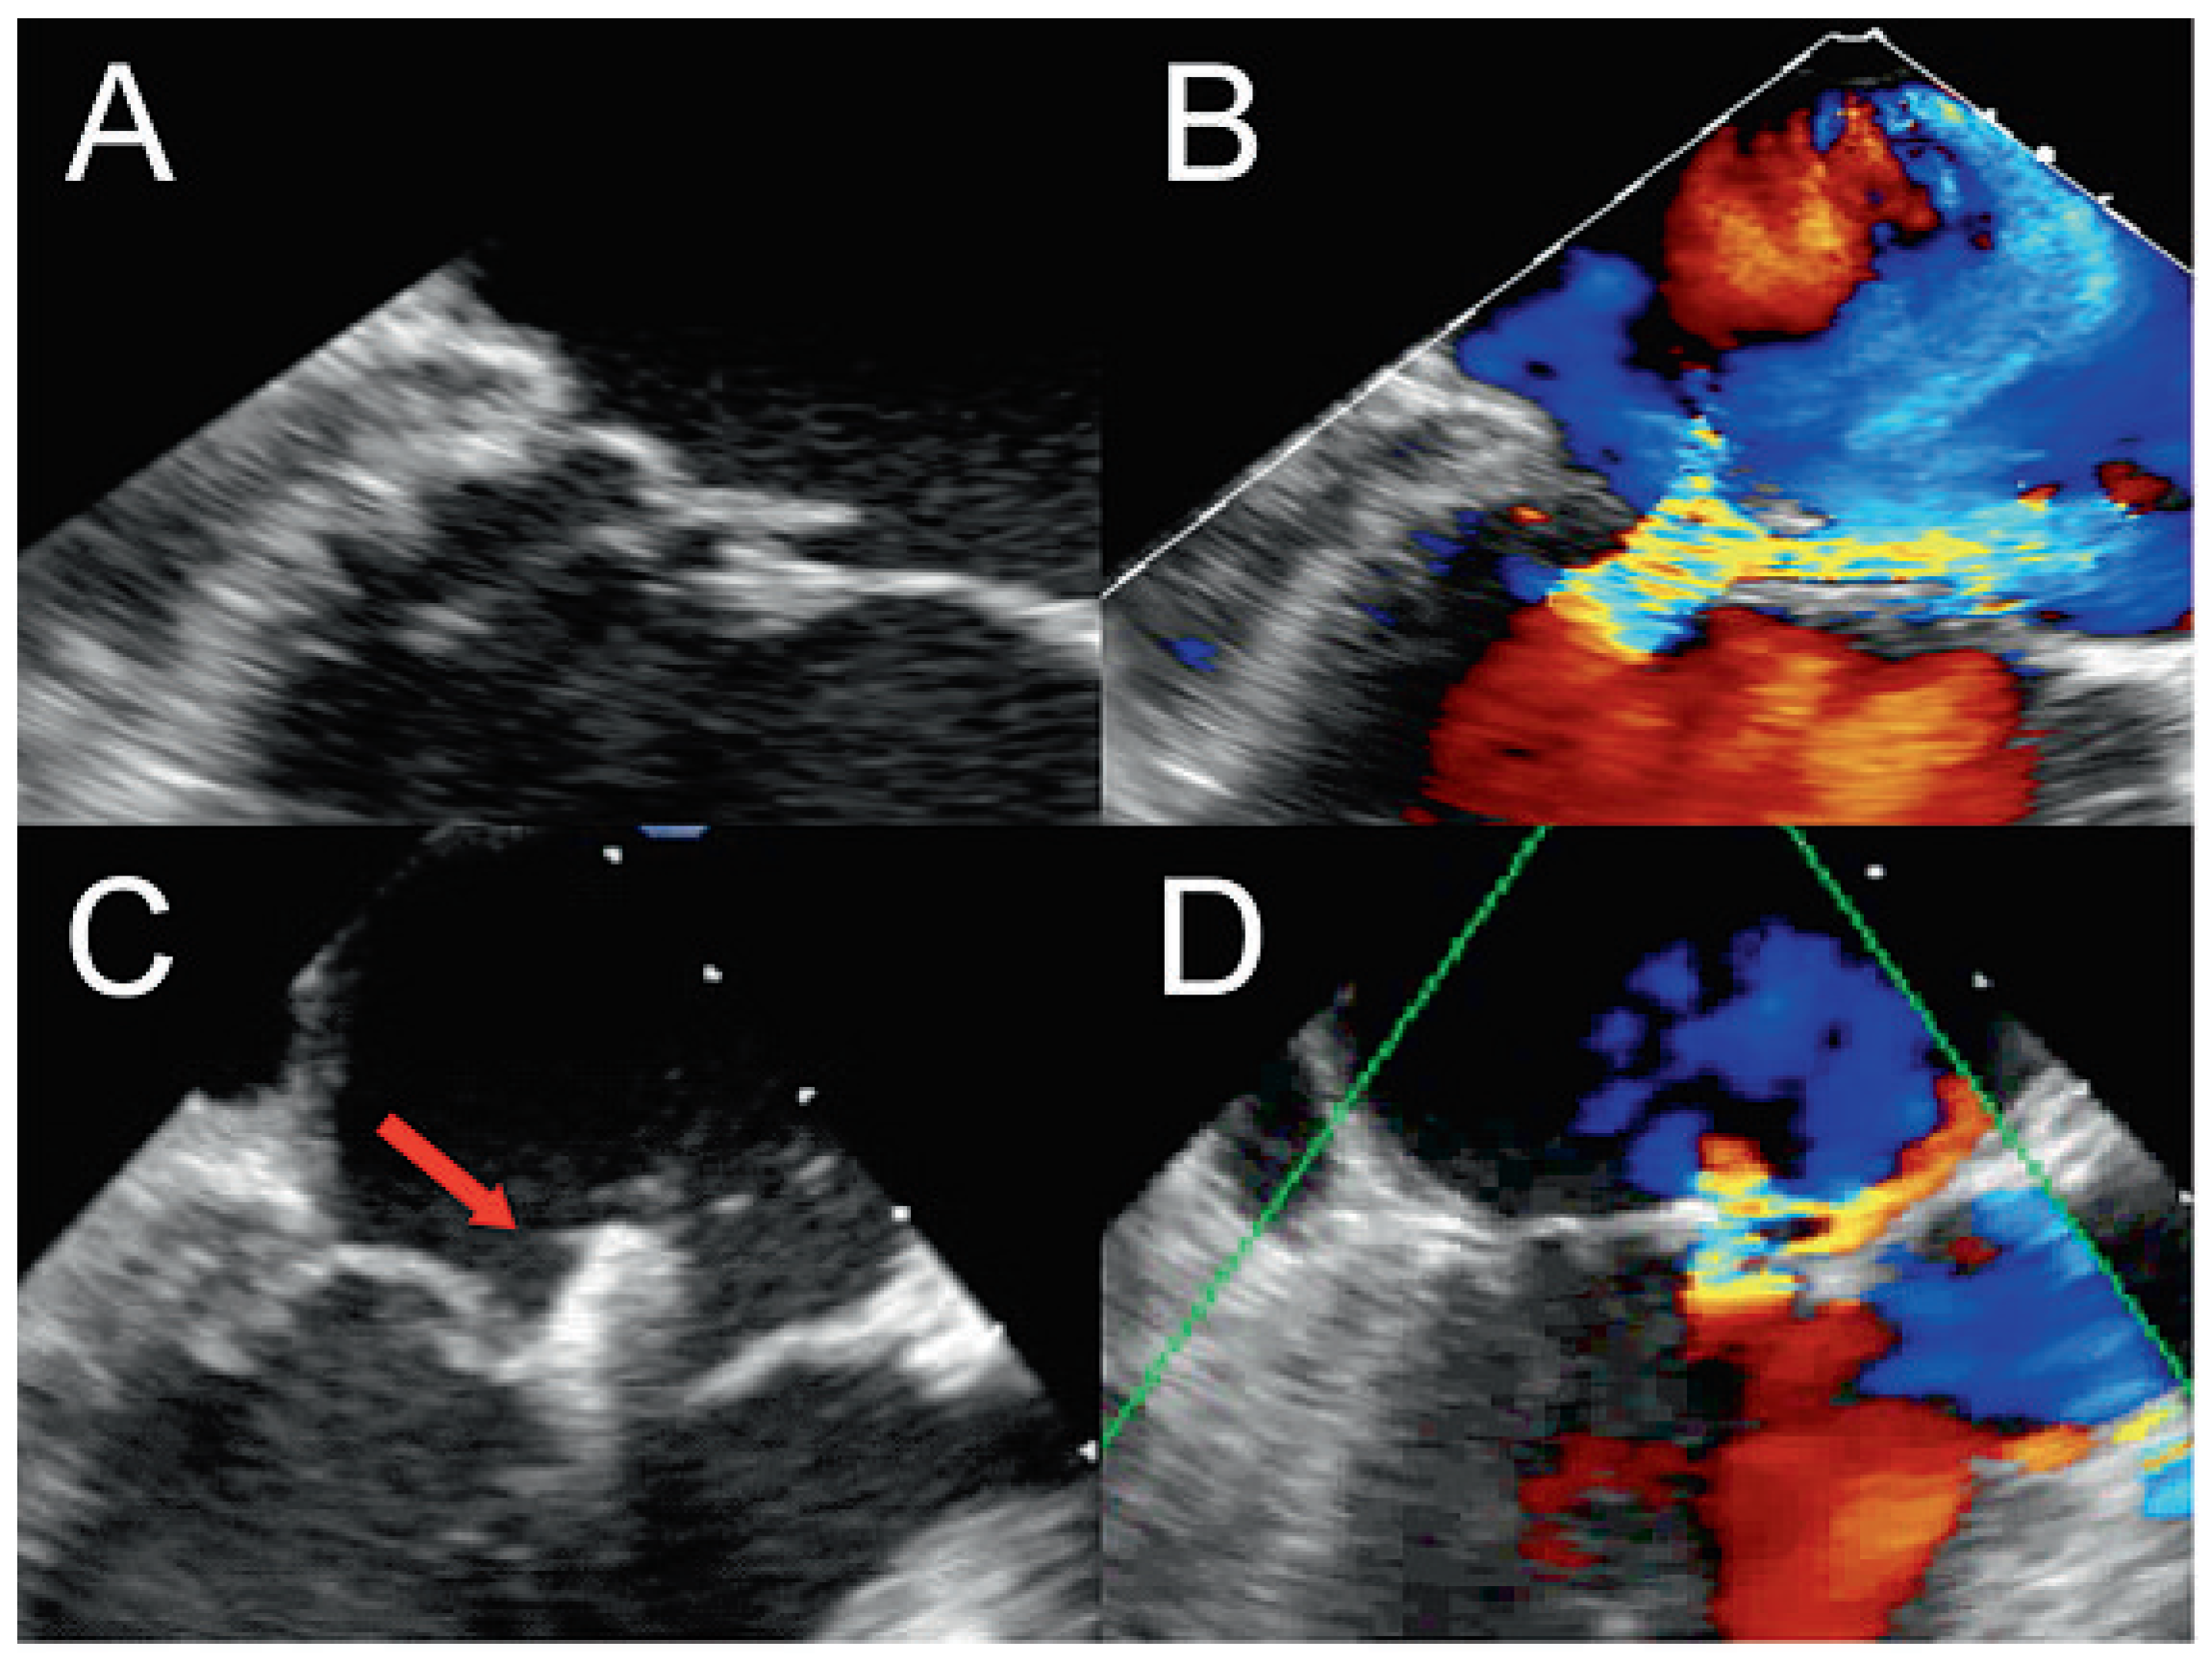

After gaining access through an 8 french sheath via the right femoral vein, transseptal puncture was performed under TEE and fluoroscopic-guidance, and an Amplatz-Super-Stiff® catheter was advanced into the left atrium (fig. 3A–C). Changing to a MitraClip-guide catheter, the clip delivery system was advanced via the left atrium (fig. 3D) into mitral position (fig. 3E). The system allows repositioning of the device under echocardiographic control until optimal placement has been found. This meant, before releasing the Clip (fig. 3F), that it could be repositioned until echocardiographic control showed the correct position of the device with mild residual regurgitation (fig. 4). 3-dimensional echocardiographic reconstruction images allowed the positioning and adjusting of the clip (fig. 5A) and the open and closed mitral valve after MitraClip® placement (fig. 5B and 5C) to be seen. The patient could be extubated in the catheter lab directly after clip implantation. The in-hospital recovery was uneventful and the patient could be discharged home three days after the intervention. During her four-week follow-up, the patient was in excellent health and reported a substantial improvement of her symptoms, reducing her exertional dyspnoea symptoms down to NYHA I–II. Echocardiographic control showed the MitraClip® in an optimal place with a residual mild-moderate regurgitation jet. On the chest x-ray film, the metallic clip can easily be identified (fig. 6).

Figure 4. Two-dimensional echocardiogram showing the flail posterior leaflet (A) with severe mitral regurgitation on colour Doppler (B). MitraClip® (red arrow) with mild residual regurgitation after placement (C) and as seen with colour Doppler (D).